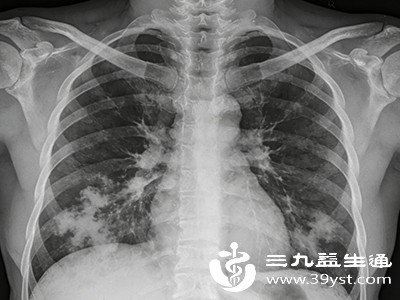

一旦出现上述肺炎早期症状,尤其是高热持续不退、咳嗽剧烈、伴有胸闷呼吸困难时,应及时到医院就诊,进行血常规、胸部X线或CT等检查,明确诊断。